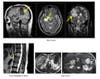

Medical findings reveal possible cause of spinal disease through use of an upright MRI scan.

The observations were made possible by use of the company’s upright scanning device, called the UPRIGHT® MRI, which allows an individual to simply walk in and be scanned. The machine scans the whole body in different positions such as lying down, standing, or bending rather than just on his/her back. The new images have resulted into complete new clinical indications, particulary for the spine and joints.

Damadian and co-researcher, David Chu, discovered obstructions of the CSF flow in all eight patients in the study and, in seven out of eight patients, the obstruction was more pronounced when the patient was in the upright position. The UPRIGHT® MRI also revealed that these obstructions were the result of structural deformities of the cervical spine, induced by trauma earlier in life.